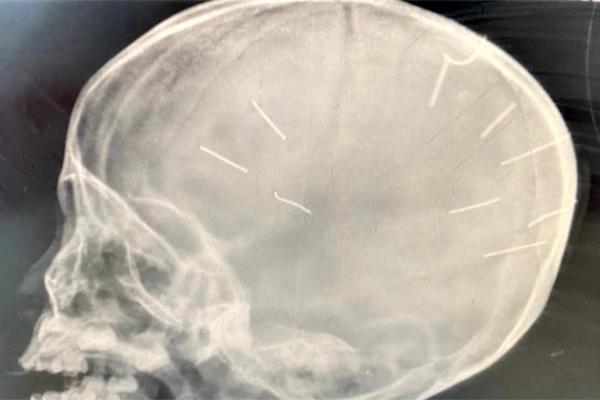

Trước đó chiều 17/1, Bệnh viện Đa khoa Thạch Thất tiếp nhận một bệnh nhi 4 tuổi nhập viện trong tình trạng hôn mê, co giật. Sau đó, bệnh nhi được chuyển lên Bệnh viện Đa khoa Xanh Pôn. Trường hợp này là bé gái Đ.N.A. Sau khi tiến hành chụp cắt lớp, dựng hình nhận thấy 9 đinh gỗ ở sọ và tổ chức não của bé.

Gần nhất, khoảng 8 giờ ngày 17/1, nhân lúc người yêu đi vắng, Huyên đã dùng tay tát nhiều lần vào mặt bé A. Thấy bé khóc, Huyên tiếp tục dùng 1 quả tạ loại 2 kg đóng 9 chiếc đinh dài khoảng 2,1 cm vào xung quanh đỉnh đầu cháu.